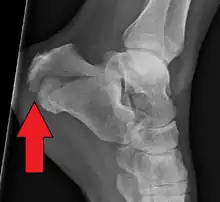

| X-ray of a fractured calcaneus | |